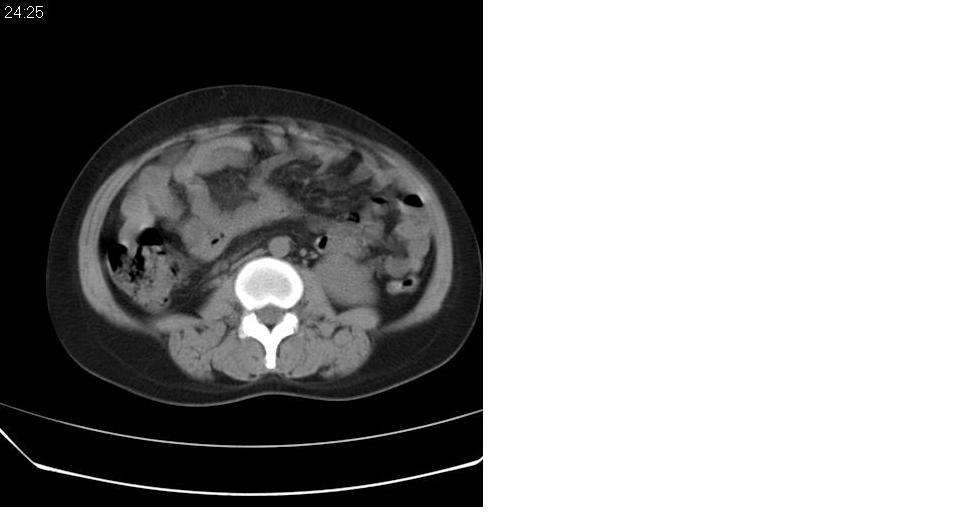

女 35岁,下腹部坠感疼,其它病史不详。图象顺序有点乱。

定位于盆腔附件,有囊性密度,有脂肪密度、还有骨密度;应该是比较典型的卵巢畸胎瘤。